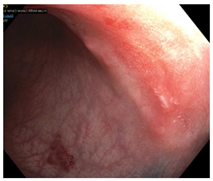

| Endoscopy | Flat white scar Telangiectasia Absence of ulcers and mucosal nodularity | Small mucosal nodules/minor mucosal irregularities Superficial ulceration Mild, persistent erythema of the scar | Visible tumor |

| Endoscopic Finding | |||

| Flat, white scar | ![]() | ![]() | ![]() |

| Telangiectasia | ![]() | ![]() | ![]() |

| Small mucosal nodules, minor mucosal irregularities | ![]() | ![]() | ![]() |

| Superficial ulceration | ![]() | ![]() | ![]() |

| Persisting erythema of scar | ![]() | ![]() | ![]() |

| Complete Response | Near-Complete Response | Incomplete Response |